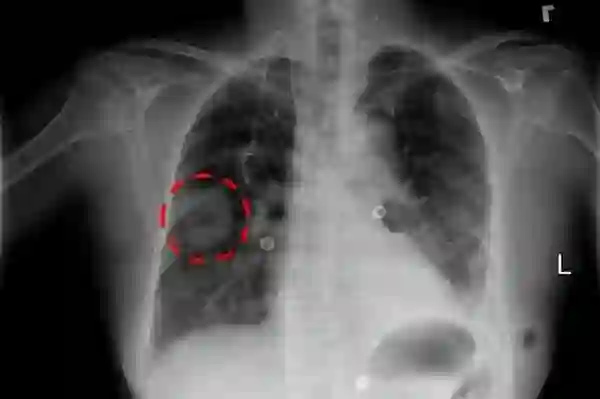

B. 常见胸部疾病的8个可视化实例(略)

D.使用弱监督深度神经网络的两个疾病定位样本